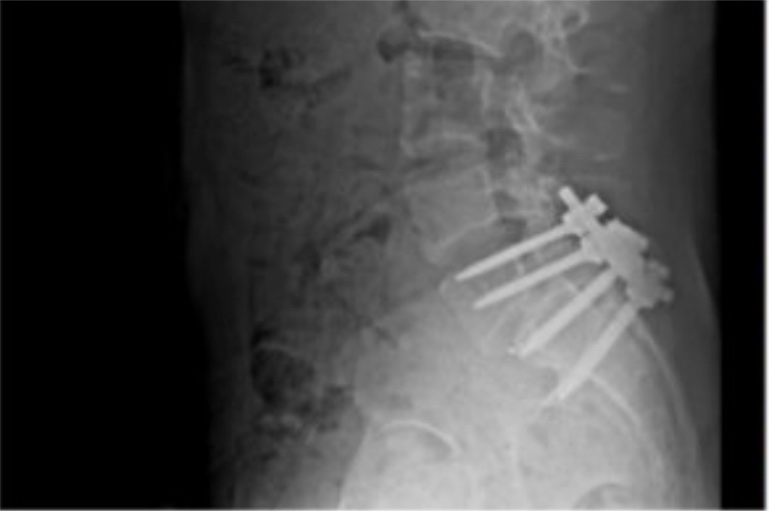

The X-ray image is from a profile photo he had pinned to one of his accounts. The photo with officer holding his neck is a still image pulled from today's Reuters video, as he entered the courthouse, shouting angrily.

I thought the surgery appeared to be lower back, not the neck. Am I wrong?

It was his lower back that was repaired. This is just pain compliance via pressure point. It’s a standard move and completely harmless.